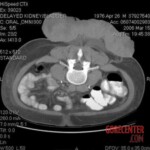

On examination, he presented with a large foul-smelling mass on his lower back measuring 22 × 25 × 7 cm, with central necrosis (13 × 12.5 cm), and an enlarged left inguinal lymph node. CT imaging showed tumor invasion into subcutaneous tissue and a 15 cm metastatic lymph node. Small lung nodules were suspicious for metastases, but too small for biopsy. A biopsy of the primary tumor revealed a poorly differentiated high-grade malignant melanoma. The tumor was S-100 positive, MART-1 negative, and rarely HMB-45 positive. He was staged as having stage IV disease.